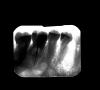

Lili4ka Опубликовано 13 июля, 2011 Поделиться Опубликовано 13 июля, 2011 Здравствуйте! Проблема с зубом. Лечили и уничтожили нерв в начале 90-х каким-то препаратом, который повлиял на цвет зуба, потом в 2000 кусок откололся, снова пломбировали и вот в конце мая 2011 начала болеть десна вокруг зуба, причем периодически с обеих сторон. Местный дантист посмотрел, сказал, что воспален десневой карман, но проблема может быть в самом зубе, и направил меня к эндо- специалисту, так как предполагал необходимость в переделке корневых каналов. День назад эндо-специалист сделал приложенный снимок зуба, и сказал, что он не сможет работать с каналами, так как зуб сломан основательно, ремонтировать нет смысла, только удалять. Посмотрите, пожалуйста, как Вы считаете, действительно ли ничего нельзя сделать с зубом? Я в Канаде, и у меня нет большого выбора врачей, к сожалению. Спасибо заранее! Ссылка на комментарий

Scrabble Опубликовано 13 июля, 2011 Поделиться Опубликовано 13 июля, 2011 Похоже, и правда перелом. Тем более, если локально(в области трещины) зондируется карман. Ссылка на комментарий

Scrabble Опубликовано 15 июля, 2011 Поделиться Опубликовано 15 июля, 2011 Если трещина-только удалять Ссылка на комментарий